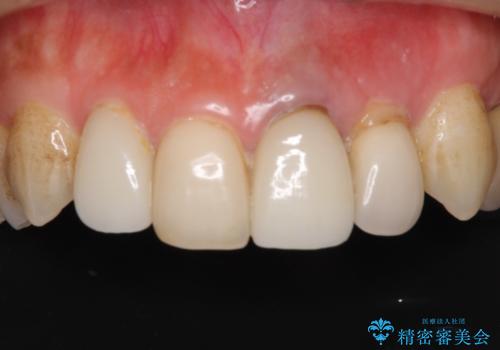

歯肉移植を用いた前歯のオールセラミックブリッジ

- 前歯が折れてしまい、ブリッジによる補綴治療を希望して来院された患者様です。

折れている前歯は抜歯をし、痩せてしまう歯肉は移植術により増大させることで審美面を回復した後、オールセラミックブリッジにて補綴することとしました。

インプラントかブリッジか悩むところでしたが、既に治療されている前歯のクラウン周りの変色が気になっていたため、ブリッジにより色調を合わせたオールセラミックを装着することを選択しました。

歯肉ラインや歯の形態、色調を整えることができ、患者様には大変満足していただきました。